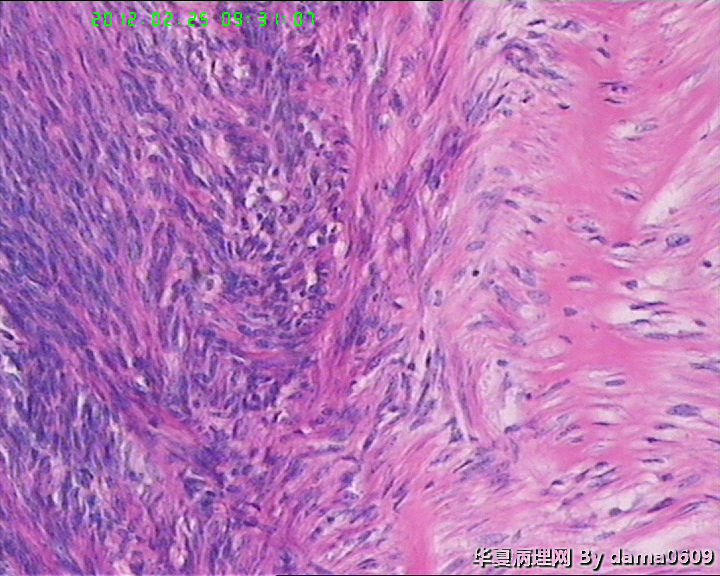

患者女性,48岁。临床未提供病史。

妇科以“子宫肌瘤”手术,术中子宫光滑、与周围无粘连。

追问患者家属病史,曾以药物治疗子宫肌瘤,具体情况不详。

巨检:次全切子宫,v:9.0x7.0x5.5cm,肌壁间见两枚肌瘤样结节,一直径0.6cm,无特殊;另一直径7.0cm,切面实性、质中、灰白、编织状、隆起、与周围肌层界限清。二者均呈典型平滑肌瘤外观。但体积大者,中心处局部见灰黄绿色坏死灶,直径约2.0cm,不规则,中间有点状红色区。

学生问题:1、这样的坏死在子宫平滑肌瘤中常见到,肉眼观界清,镜下坏死灶与周围正常组织陡然分界,无移行带,又不见明显炎细胞浸润,故怀疑是否为凝固性坏死??坏死灶内坏死平滑肌细胞无异形性,但轮廓清晰可辨,是否为“鬼影细胞”?

2、此例坏死灶周围平滑肌组织核分裂像很容易见到,时而一个高倍视野竟有四个,如何解释、诊断?再者学生对平滑肌细胞核分裂像也不肯定,请老师指教,应该不是核固缩。

应为梗死.

本例应为平滑肌瘤伴玻璃样坏死。

细胞的轮廓还在,是梗死。